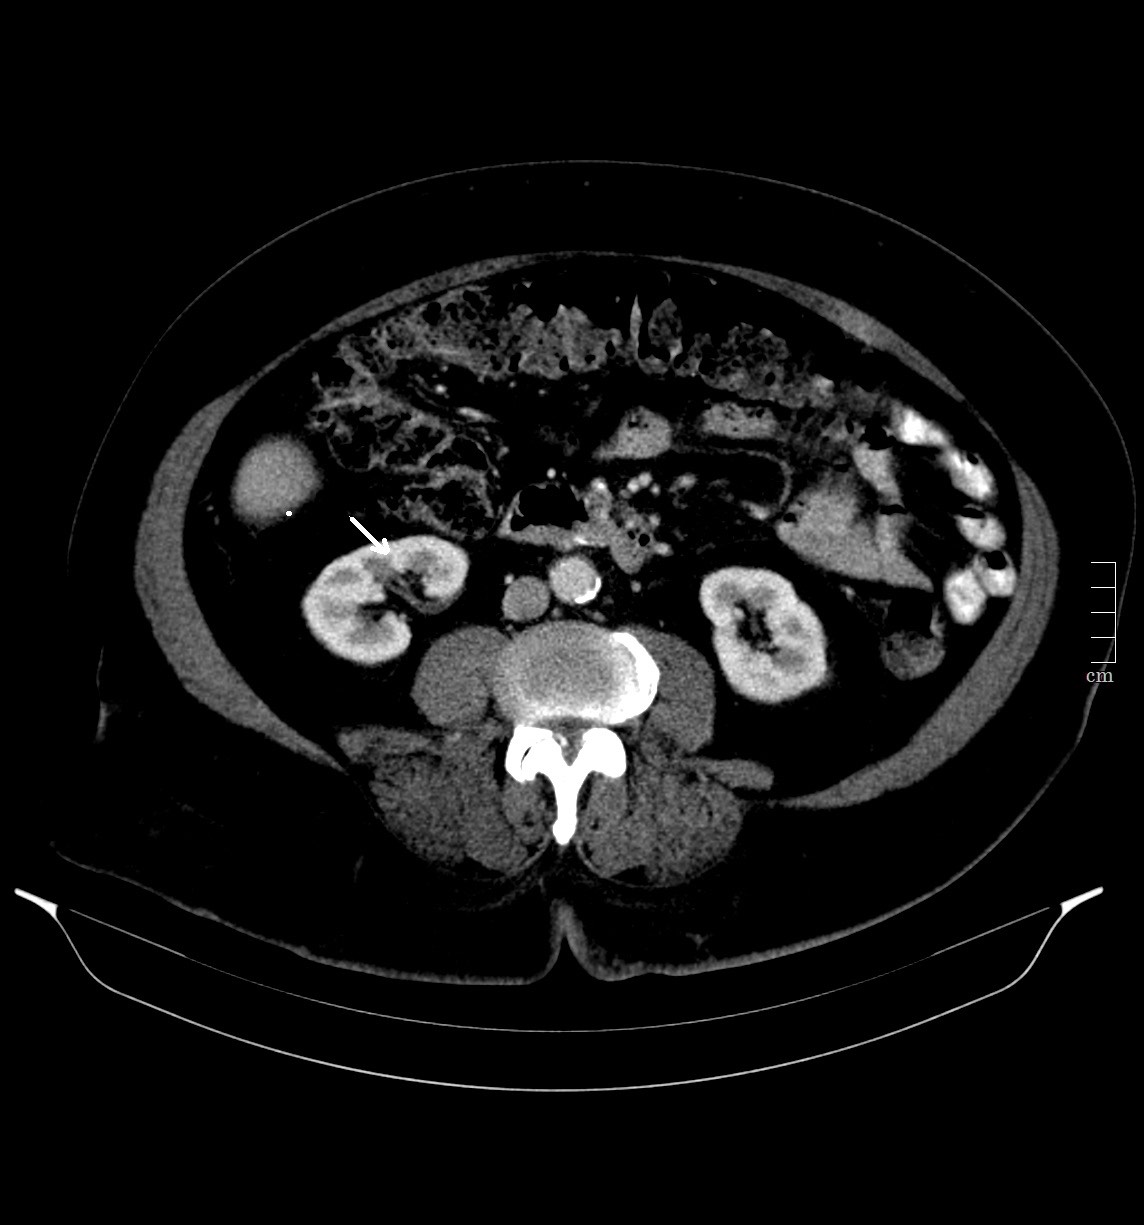

2914. Структура, указанная стрелкой, является